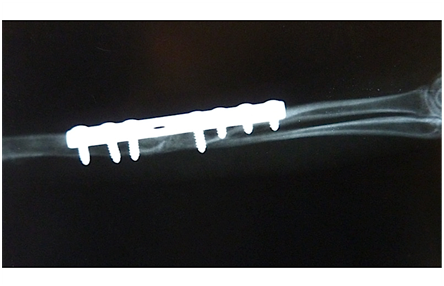

Six months old hare was found near a suburban area, immobile with several injuries. It was presented at the Surgery Clinic for evaluation of a third grade right forelimb lameness. The initial examination showed a bright, alert and stabile animal. Full orthopaedic and neurological examination was performed. Radiographic examination from anteroposterior and lateral views confirmed a old, closed, complete, non-comminuted, transverse diaphyseal fracture of right radius and ulna (Figure 1). Osteosynthesis was performed to achieve anatomical repositioning of fragments and to restore normal biological function of the limb.

Figure 1 Old non-union fracture of radius and ulna in young brown hare. Radiograph shows a formed callus and fused radius and ulna under angulation. Fracture line is still visible.